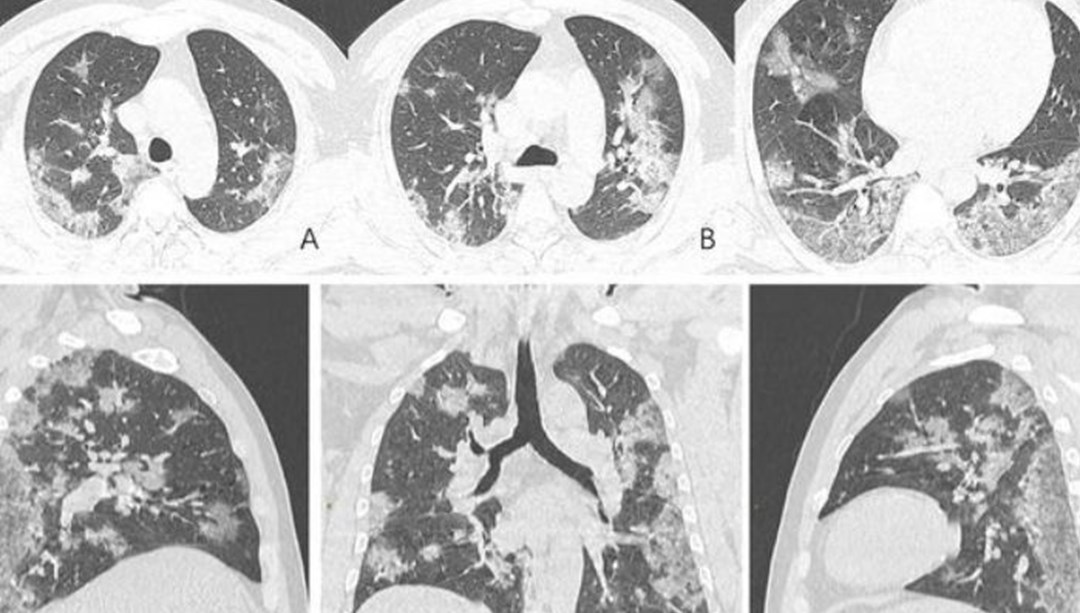

Burakhan Sönmez'in tedavi sürecini yürüten Gazi Üniversitesi İç Hastalıkları Yoğun Bakım Öğretim Üyesi Doç. Dr. Melda Türkoğlu, corona virüsün üst ve alt solunum yolu enfeksiyonuna yol açan bir virüs gibi görünmesine rağmen tüm vücudu etkileyen multisistemik bir hastalık olduğuna dikkat çekti.